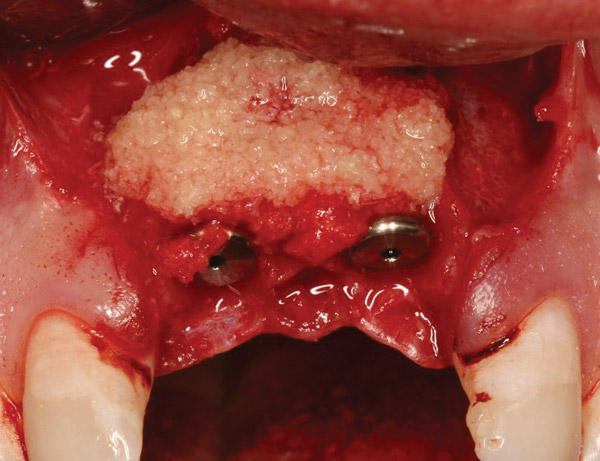

Figure 15  After extraction and 3 months of healing, two implants were placed in ideal position and with primary stability at sites Nos. 8 and 9. Implants were stable. Dehiscence defects exposing 13 threads were produced.

Figure 15

Figure 16  Freeze-dried bone allograft over a layer of autogenous bone was used to cover the dehiscences.

Figure 16

Figure 17  A bioabsorbable collagen membrane covered the grafts to promote hard-tissue regeneration.

Figure 17